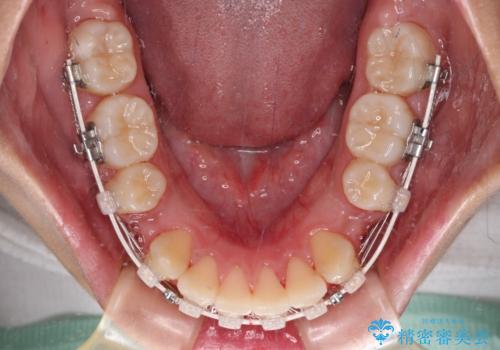

- 矯正装置

- 審美装置

- 2年2ヶ月

上下左右の第一小臼歯4本を抜歯し、ワイヤー装置での抜歯矯正を行うこととしました。

右側の咬み合わせは、上顎がやや前方位にある状態であったので、通常は補助装置を併用するのですが、高校生ということで補助装置なしで治療を行うこととしました。